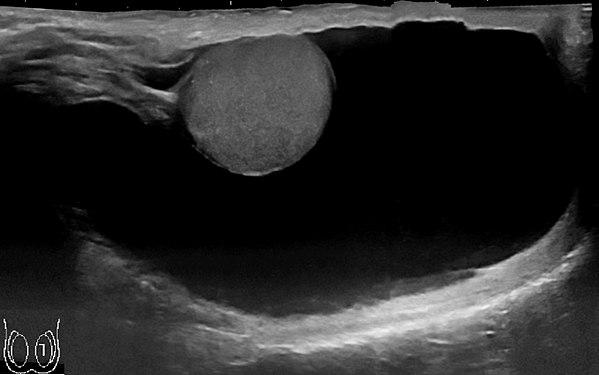

С помощью УЗИ мошонки и паховых каналов подтверждается диагноз водянки яичка у мальчиков, исключается более серьезная патология (рак яичка, воспаление или перекрут яичка или его придатка). Кроме этого, УЗИ мошонки является высокочувствительным методом в определении вида водянки яичка у мальчиков (сообщающейся или несообщающейся). В дополнение к основному исследованию целесообразно проведение УЗДГ сосудов мошонки.

Для установления правильного диагноза используется УЗИ – ультразвуковое исследование паховых каналов и органов мошонки и дуплексное исследование сосудов яичка. УЗИ нередко позволяет обнаружить проблему с другой стороны – например, невидимую при осмотре паховую грыжу или кисту семенного канатика. Иногда увеличение мошонки и паховой области то появляется, то исчезает, причем при осмотре врача может отсутствовать. Тогда решить вопрос о диагнозе помогает фотография, выполненная при появлении припухлости в мошонке или паховой области сделанная родителями.

Для установления правильного диагноза используется УЗИ – ультразвуковое исследование паховых каналов и органов мошонки и дуплексное исследование сосудов яичка.

УЗИ нередко позволяет обнаружить проблему с другой стороны – например, невидимую при осмотре паховую грыжу или кисту семенного канатика.

- УЗИ органов мошонки и дуплексное сканирование сосудов. Ультразвуковое исследование позволяет определить гидроцеле яичка, причины его вызвавшие, наличие опухолей семенного канатика.